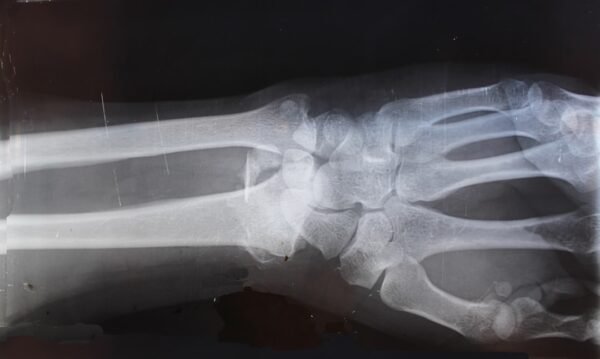

AI in radiology and medical imaging for 2026

Here’s a look at what AI might bring to radiology and medical imaging in 2026, keeping it practical and to the point. AI’s Role in Radiology: More Than Just Hype So, what’s the real deal with AI in radiology and medical imaging by 2026? It’s going to be about integration and refinement, not a complete […]

AI‑driven diagnostics in medicine: what’s new in 2026

AI-driven diagnostics in medicine is seeing some meaningful advancements as we head into 2026. Rather than grand, paradigm-shifting overhauls, what we’re noticing more are focused improvements. These are making existing diagnostic processes more efficient and, in some cases, opening doors to earlier detection. It’s less about replacing human clinicians entirely and more about providing them […]